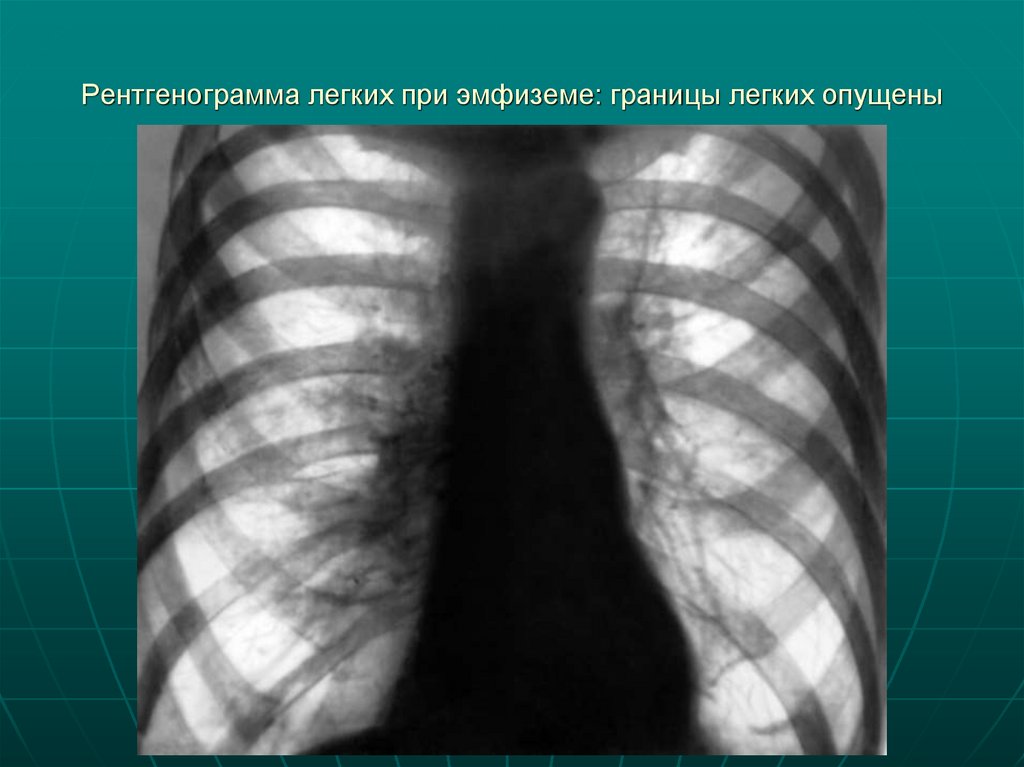

Рентгенограмма легких при эмфиземе: границы легких опущены

18. Рентгенограмма легких при эмфиземе: границы легких опущены